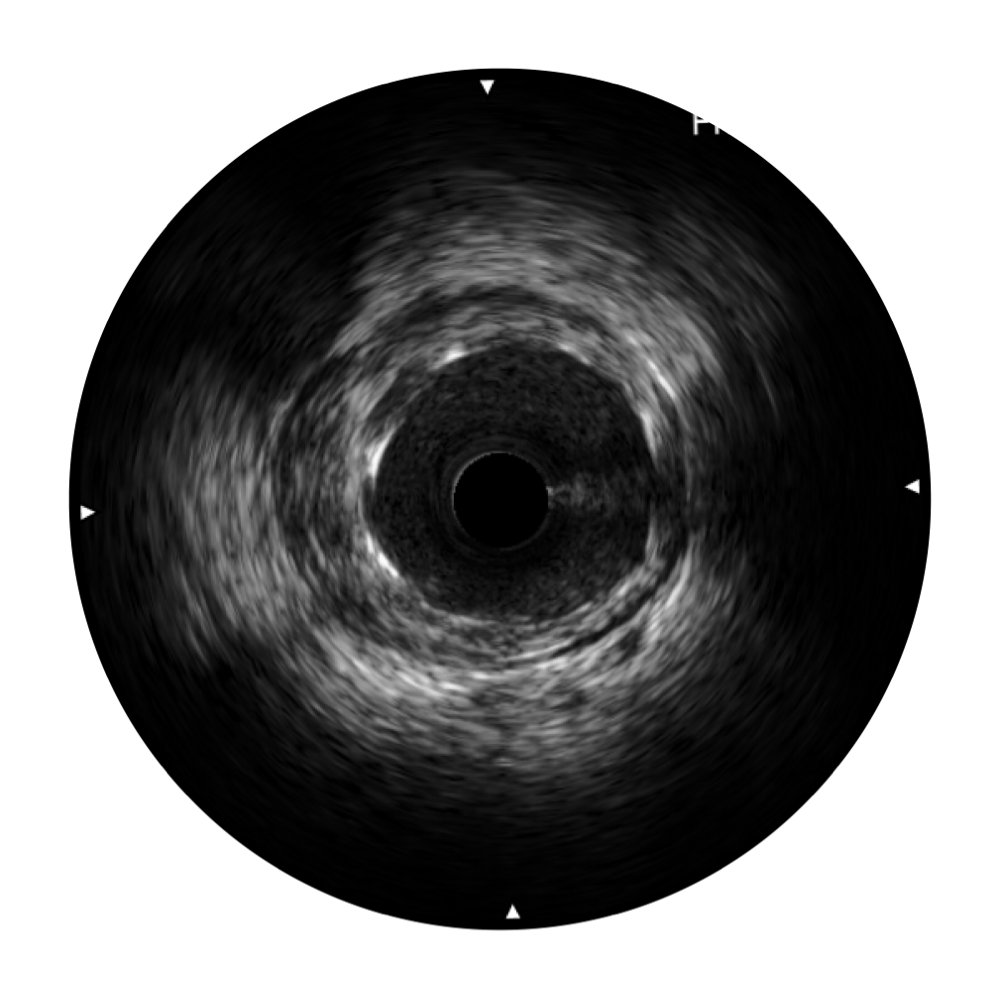

• 传统IVUS图像

对比传统IVUS导管成像,16877太阳集团宽频IVUS图像的近场支架梁显影更细腻,远场中膜外血管仍清晰可辨,兼顾远中近,兼顾分辨力与穿透深度

临床图

远场分支血管及导丝

支架内血栓

组织脱垂